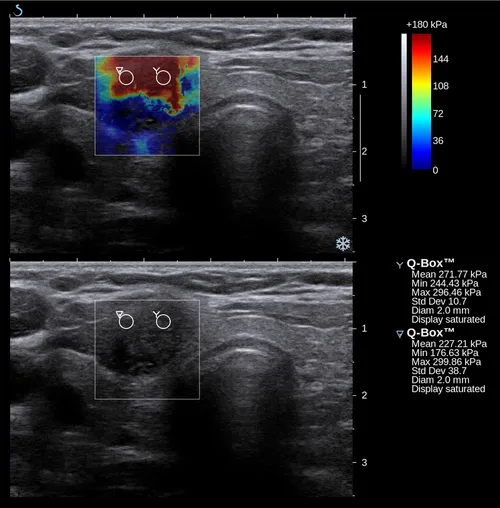

Élastographie thyroïdienne

L’élastographie thyroïdienne est une nouvelle technique prometteuse dans l’évaluation d’un nodule thyroïdien. Elle permet tout simplement une palpation virtuelle du nodule qui ne l’est pas cliniquement.

Cette technique a été développée pour obtenir des informations sur la rigidité d’un tissu de façon non invasive. Étant donné que la thyroïde est un organe assez superficiel, il est possible grâce à cette technique d’obtenir des informations quand à la dureté du tissu et notamment d’un nodule suspect.

La plupart des tumeurs malignes sont caractérisées par la présence d’un parenchyme anormalement rigide qui est la conséquence d’une proportion anormale de collagène et de myofibroblastes dans le tissu.

Certaines tumeurs bénignes peuvent malgré tout présenter une rigidité importante comme les histiocytofibromes. Cette technique permet donc d’orienter le diagnostic.